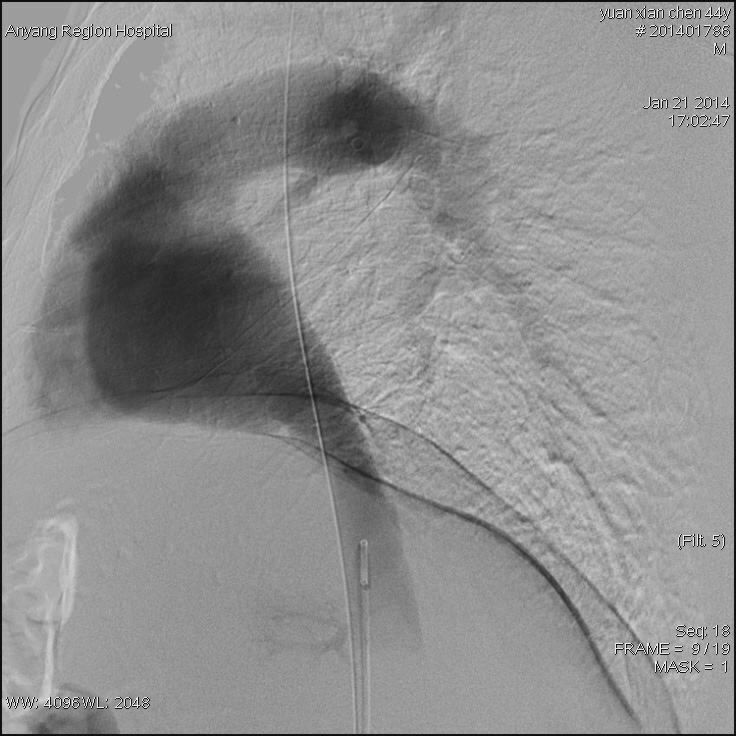

接受治疗的是一位44岁男性患者,该患者常年消化不良,身体异常瘦弱,肝脾肿大,双下肢静脉曲张合并腹壁静脉曲张,经核磁影像检查,诊断为布加综合征,考虑为下腔静脉肝后段膜性闭塞病变。我院介入科主任高毅组织科室医务人员认真研究患者病情,并详细制定出多种介入开通方案。1月21日,为患者进行了介入治疗。手术中,经穿刺股静脉与颈内静脉双向造影后,进一步明确了该患者为膜性闭塞。采用破膜针开通闭塞段,引入加硬导丝,交换引入较大球囊扩张后,患者下腔静脉瞬间畅通,下腔静脉压力明显下降,下肢静脉及腹壁静脉曲张立即消失,六小时后患者即下床活动,困扰患者多年的头晕等症状也随之消失。